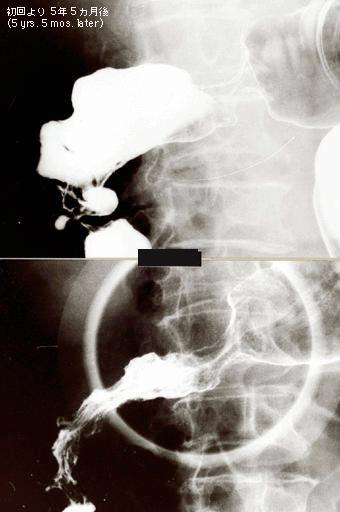

陈旧性的大肠结核病巢内发生大肠癌,影像追溯其经过的病例 (东京都台东区某医院病例)

[ Image ID:533 ]

炎症性・溃疡性疾患/结核

部位(按器官分)

大肠/占据大肠的2个以上区域

检查方法